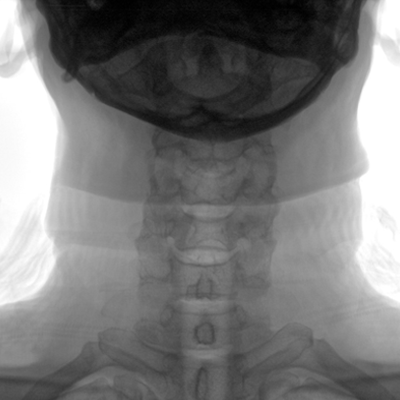

大尺寸動態平板探測器,高DQE、低噪聲、圖像清晰。采用多分辨率圖像增強處理技術,不同部位不同圖像處理算法,滿足客戶多樣化的需求。

采用智能變頻脈沖透視技術,優化圖像質量的同時降低輻射劑量,呵護醫患健康